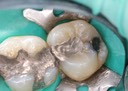

Joe Cha #18 amalgam removal